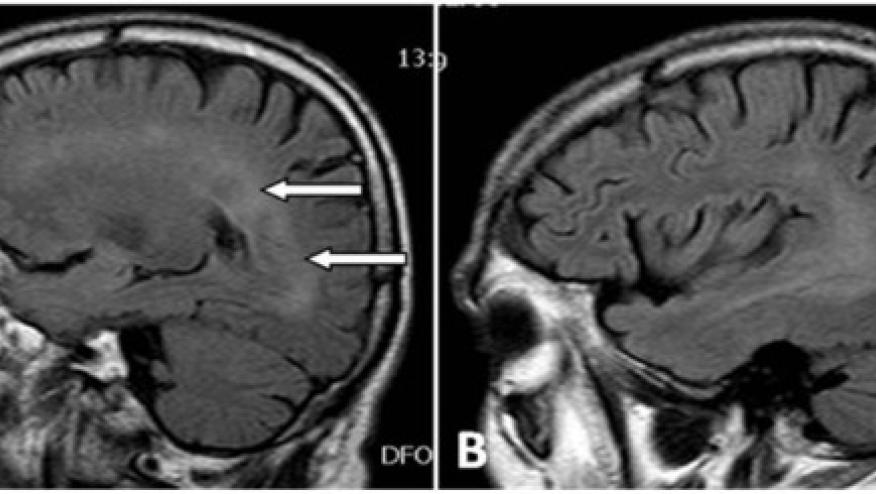

CNS vasculitis has many mimics that Dr. Hajj-Ali has worked on for years. There are useful clinical criteria but as we have increased our imaging capacities including improved MRI capabilities, there are now more unique and more precise techniques to assess the vessel wall. Imaging vessel walls through MRI or PET-CT can assess edema, thickness, enhancement, lesions, etc. Dr. Hajj-Ali has 2 posters looking at MRI in CNS vasculitis and wall enhancement (abstracts #0411, #0409). These considerations now need to be assessed in large prospective randomized trials

Still difficult if not impossible to diagnose CNS vasculitis by just imaging. Notoriously, neuro-radiologists tend to over-read these images, including the mentioning of "vasculitis" in just about every differential diagnosis, prompting rheumatology consults in a variety of different setting and diseases. That's the problem, since such a diagnosis would mandate immunosuppression. I have discontinued said therapy in many patients with diabetes and widespread atherosclerotic disease, diagnosed as having "CNS vasculitis". They all had a vasculopathy allright but not true vasculitis,